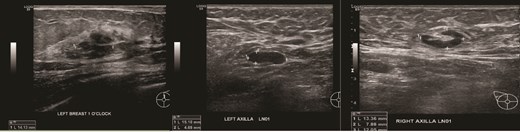

(Left) Ultrasound images of the left breast ill-defined hypoechoic mass; (Middle, Right) Ultrasound images of the axillary lymph nodes with cortical thickening and effacement of the fatty hilum.

Patient B, aged 72, was healthy and presented with left breast pain and a breast lump for 5 months. A 15 mm left breast lump was palpable. Imaging confirmed this finding and revealed bilateral axillary lymphadenopathy (Figs 4 and 5). Core biopsies of the left breast nodule and bilateral axillary nodes were diagnostic of chronic B cell lymphocytic lymphoma (Fig. 6). Positron emission tomography (PET) scan demonstrated disseminated lymphadenopathy involving cervical, mediastinum, and intra-abdominal lymph nodes. As the disease was indolent and she was asymptomatic, she was conservatively managed with active surveillance. Her breast discomfort resolved with analgesia. Follow-up imaging demonstrated stable lymphadenopathy.